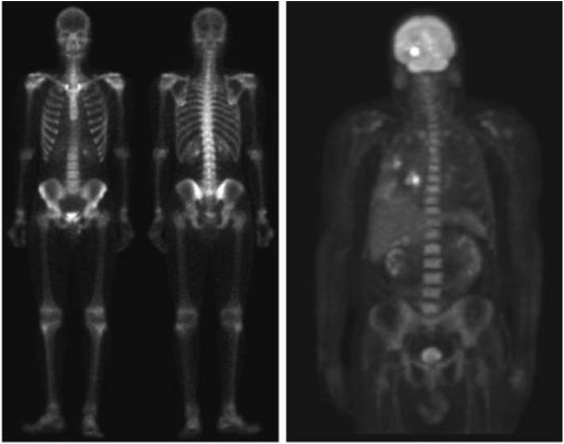

- 주요 응용분야: 의학(MRI: magnetic resonance image), 천문학

인체의 MRI 무릎, 척추

게자리 (pulsar)